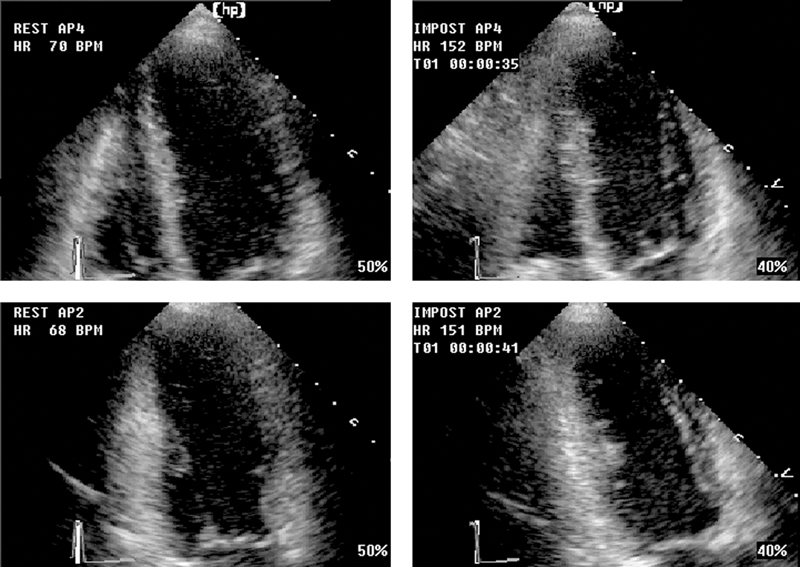

فحوصات تشخيصية لبعض امراض القلب والشرايين التاجية